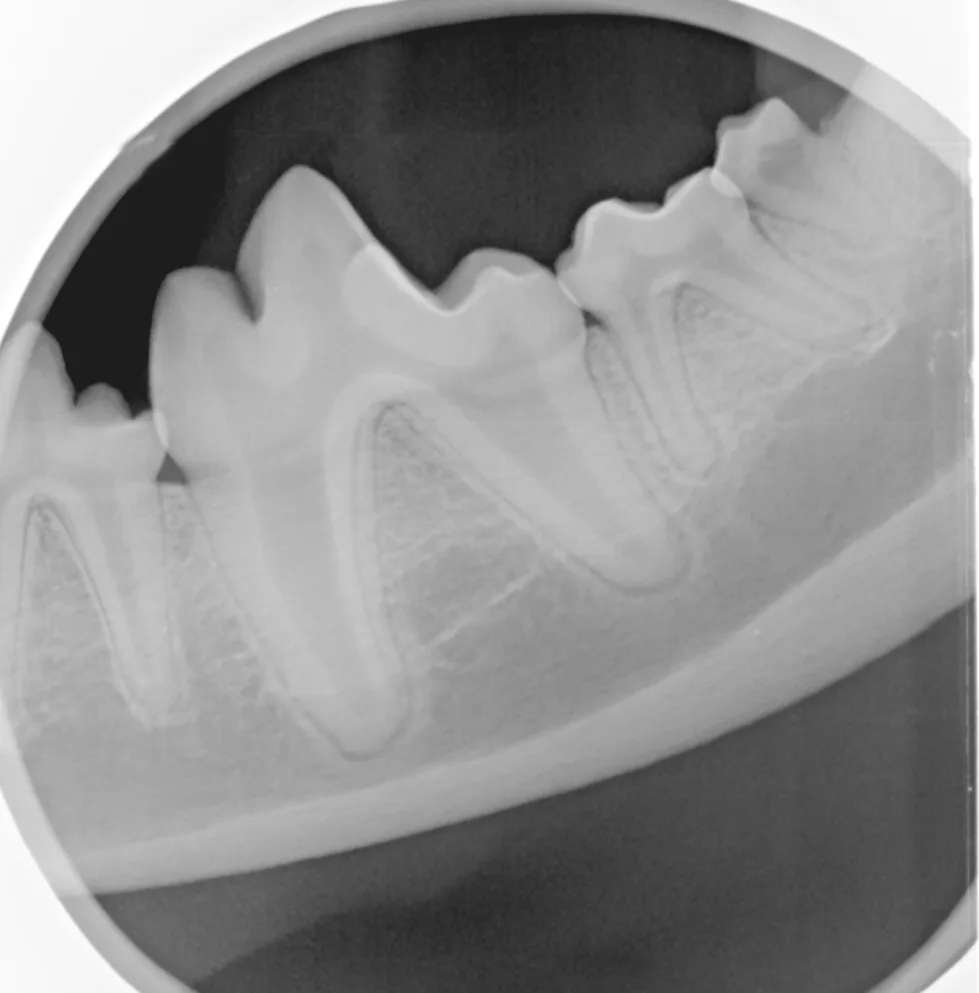

After the patient is anesthetized using multimodal pain control protocol (including a mandibular nerve block), obtain an intraoral radiograph to evaluate root structure and mandibular bone integrity.